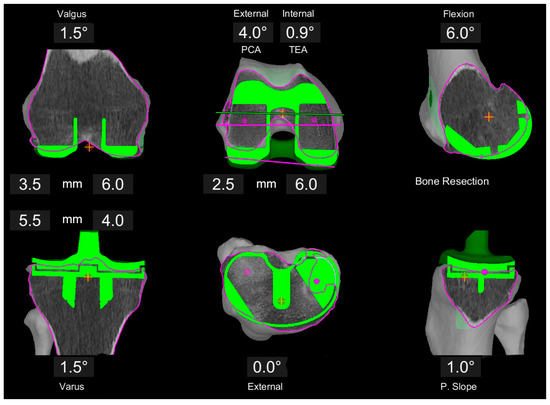

All surgeries were conducted with the MAKO robotic arm and the Triathlon PS knee system (Stryker, Kalamazoo, MI, USA). Prior to surgery, three-dimensional preplanning of the individualized component position using the proprietary MAKO software was conducted by the operating senior surgeon following the concept of kinematic alignment (KA) (Figure 1). First, the distal and posterior resections on the femur were set symmetrically at 6 mm bone resection. This results in an individual distal femoral angulation and a 0° rotation with reference to the posterior condylar axis (PCA) (individual rotation to transepicondylar axis (TEA)). In a second step, the femoral component size was defined to best reconstruct the anterio-posterior and medio-lateral dimensions without producing an overhang. Based on this position and size, the femoral flexion was adjusted to create a smooth anterior transition without notching.

Figure 1.

Example of image-based planning of the component position based on the principles of KA. Femoral resections are set to 6 mm each, resulting in 0.5° valgus position and 0.7° internal rotation with respect to the TEA. Tibia plan is preliminary at 1.5° varus, 1.5° slope and a resection level of 4 and 5 mm, respectively.